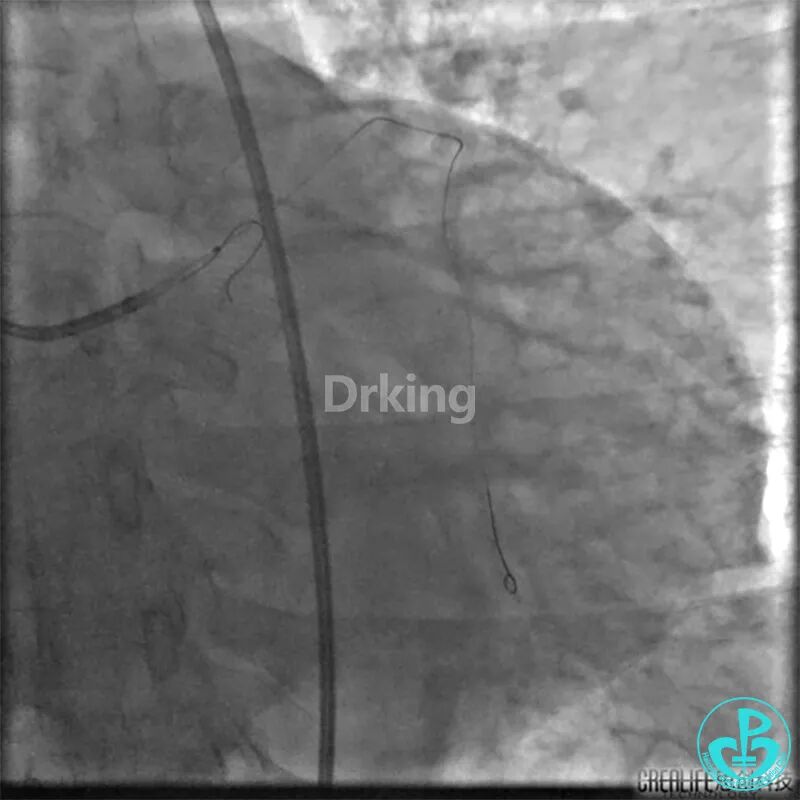

该患者近日转诊到江苏省人民医院,复查冠脉造影术,提示LCX近段扭曲严重(2处90度扭曲)的远段95%狭窄。当地医院市级及地区级医学院附属医院曾反复尝试,导丝均未能通过LCX近段扭曲处送至远段。

7F EBU指导导管到达左冠开口,把Sion导丝送至LAD远段,先后在微导管、双腔微导管、抽吸导管及2.5×20mm、3.0×15mm球囊堵闭LAD开口等各种技巧辅助支撑下,尝试Sion、BMW、Intuition、XT导丝反复塑形调整均未能通过LCX近段扭曲处送至远段。其间采用了球囊锚定、双腔微导管支撑、抽吸导管支撑、导丝塑成天鹅颈形状等技术。

经反复尝试失败后,发现由于LAD血管较粗,且LCX严重扭曲角度刁钻,而且不止一个高度弯曲(2处),以上技术实施时预进入LCX的导丝仍然会被弹入LAD。

此时反复看造影图,发现LCX有一支高位的小的OM,预想是否可以把导丝送至高位OM远段,再用双腔微导管辅助支撑下将另一根导丝通过严重扭曲处送至LCX远段呢?

以下是导丝成功通过严重扭曲病变的图: